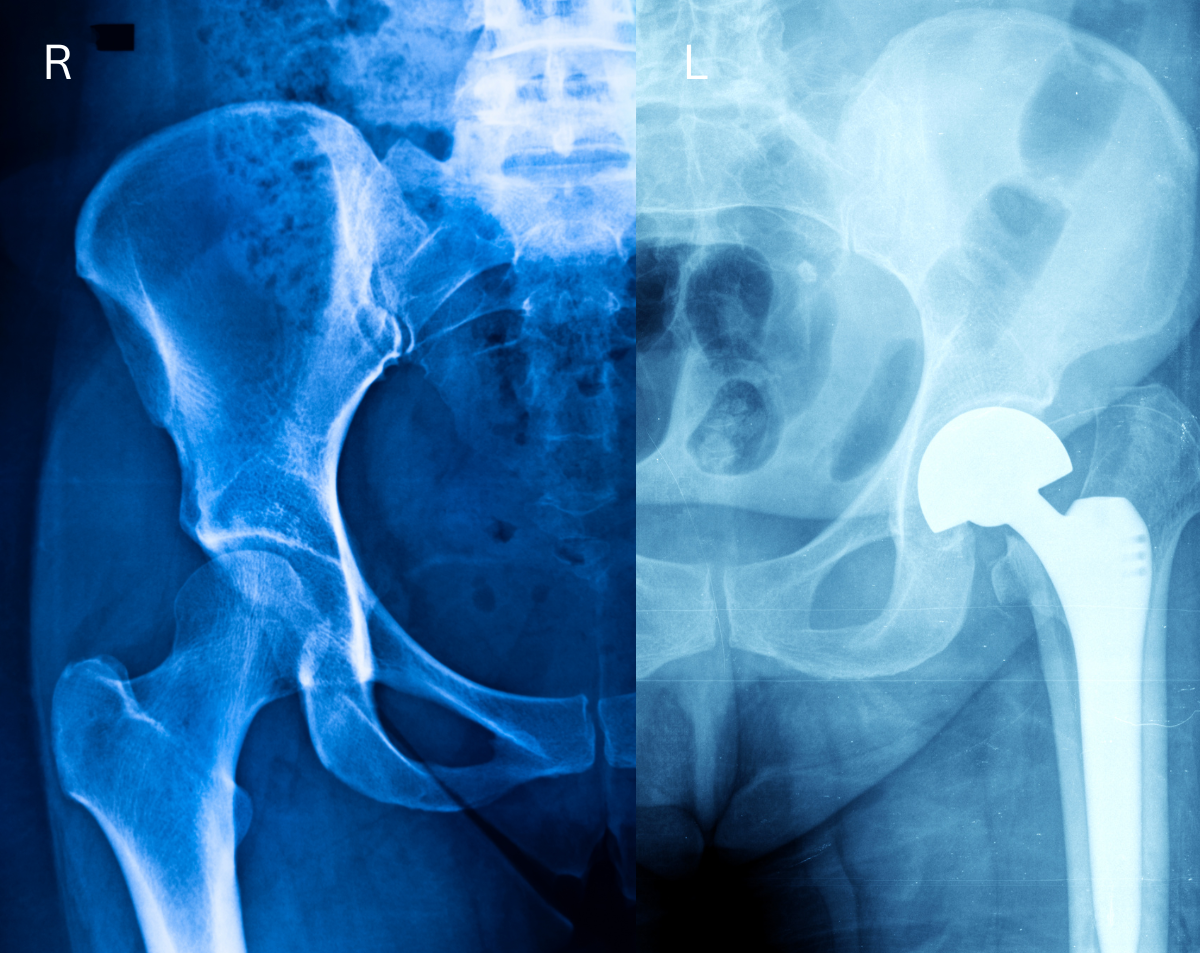

Your hip joint is one of the body’s strongest weight-bearing structures, yet it’s also vulnerable to injury and wear. A hip X-ray helps your physician identify:

Osteoarthritis and other degenerative joint diseases

Hip dysplasia or structural abnormalities

Post-surgical healing after hip replacement or repair